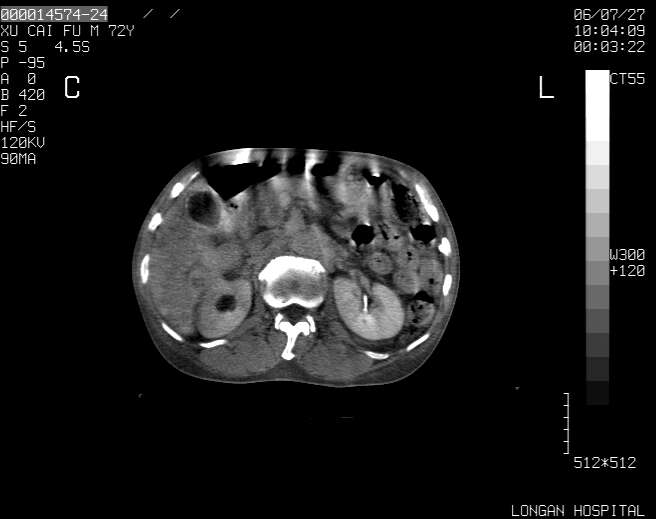

以下是引用winter在2006-7-30 20:14:00的发言:[br]1、考虑胆囊癌伴胆道侵犯并高位胆道梗阻、肝内多发转移、腹膜后淋巴结转移。[br]2、右肾轻度积水。[br]3、老人家72岁了胰腺头体尾部均较饱满,不过未见密度异常及其他异常征象。[br]4、腹水。

以下是引用jiajie在2006-7-31 7:10:00的发言:[br]考虑肝转移瘤,腹膜后淋巴结增大。[br]胃癌不能除外,建议胃镜检查。